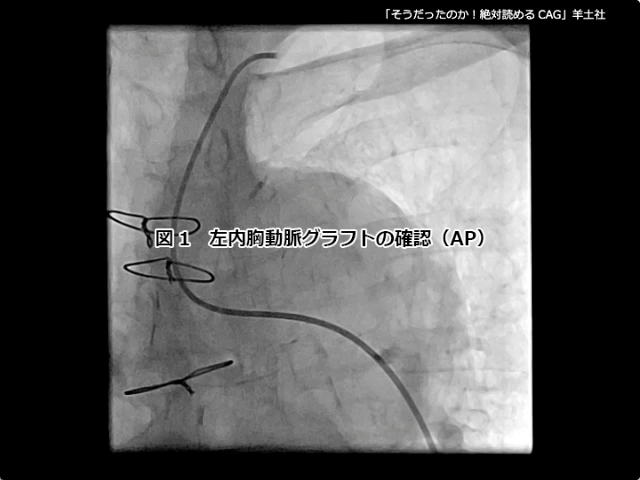

そうだったのか! 絶対読めるCAG【付録動画サンプル】